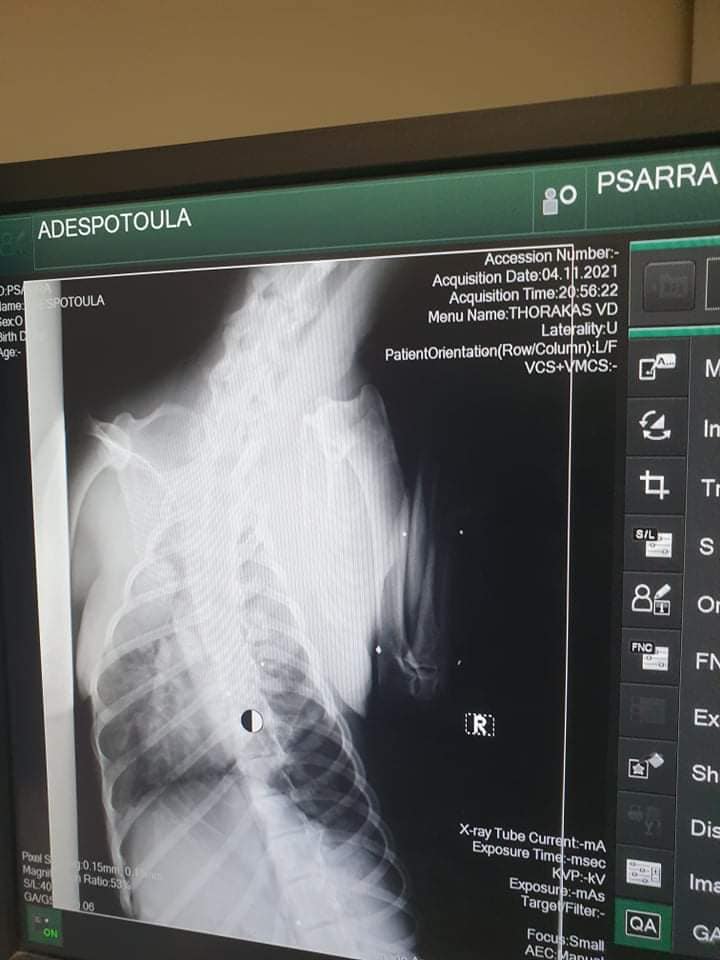

Το ζώο χειρουργήθηκε στις 9 Νοεμβρίου καθώς μεταξύ άλλων είχε και πυομήτρα. Οι ακτινογραφίες, που έβγαλε στην κλινική έδειξαν και τα πολλά σκάγια στο κορμί του – δηλαδή έχει πυροβοληθεί από κυνηγό – καθώς και το κάταγμα κνήμης και περόνης στο πόδι, το οποίο αντιμετωπίστηκε με νάρθηκα, αλλά και ο υγρό στον πνεύμονα (το όποιο αφαιρέθηκε με παρακέντηση). Είχε επίσης και εσωτερική αιμορραγία στην κοιλιακή χώρα.